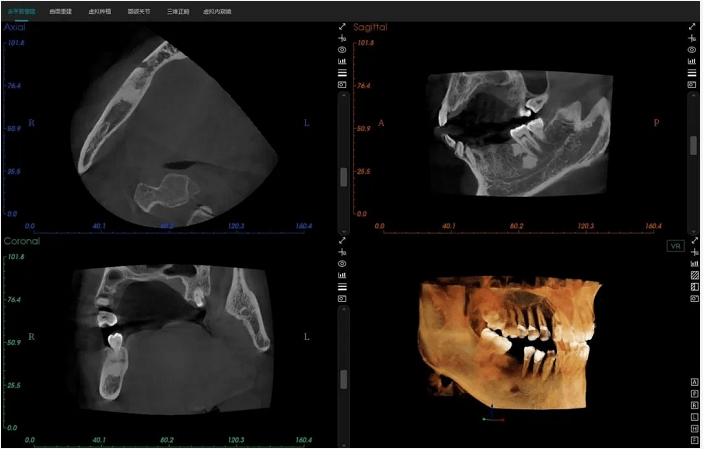

深刻剖析美亚光电三种视野的口腔cbct

图片尺寸1080x565

颊舌向宽度约7-8mm,骨质正常,无疏松影,35根尖远中见一"骨岛"影像